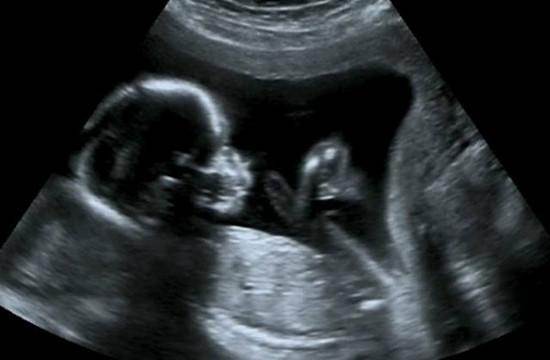

1、医学超声波检查:医学超声波检查的工作原理与声纳有一定的相似性,即将超声波发射到人体内,当它在体内遇到界面时会发生反射及折射,并且在人体组织中可能被吸收而衰减。因为人体各种组织的形态与结构是不相同的,因此其反射与折射以及吸收超声波的程度也就不同,医生们正是通过仪器所反映出的波型、曲线,或影象的特征来辨别它们。此外再结合解剖学知识、正常与病理的改变,便可诊断所检查的器官是否有病。